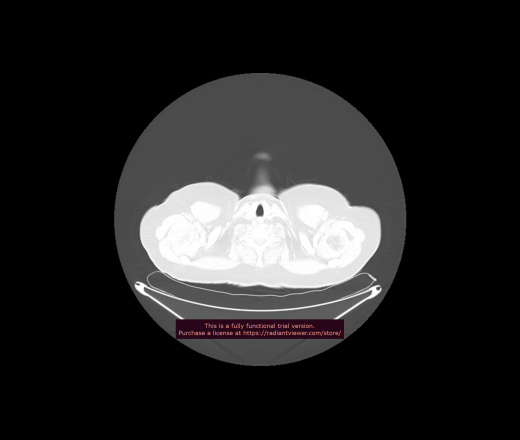

Уважаемые коллеги, если имеется интерес, сможете ли Вы спрогнозировать дальнейшее +-одинаковое течение процесса у 4 данных разных пациентов? Зацепиться где-то можно очень просто, где-то нельзя.